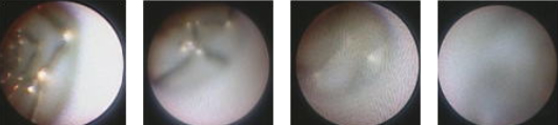

血管内視鏡

光ファイバーを挿入した内視鏡カテーテルを用いて血管内を観察することが可能な装置です。血管の性状を肉眼的に評価できるため、生体内における病理診断に匹敵する機能を有しています。冠動脈プラークの性状評価や血栓の有無、植え込まれたステントの状態評価などを直視下で行うことが可能です。

さらに大動脈内を内視鏡で観察することも可能であり、CTやMRIでは判定が困難な大動脈の動脈硬化性状を詳細に診断・鑑別することも可能です。

血管内視鏡での画像